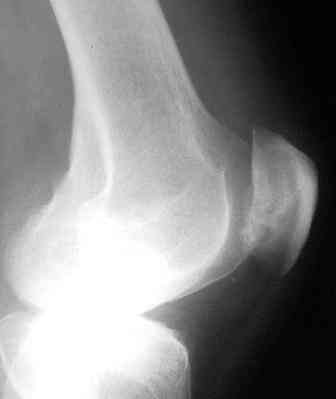

Re: Остеохондропатия надколенника?

А что конкретно беспокоит больного:хромота ,хронический синовит,есть ли характерный хруст при сгибании сустава,симтом "ладони",итп?Прежде всего надо сделать аксиальную рентгенографию по Кнудсену или еще как то или КТ.Есть возможность сделать артроскопию?-может все быть завершено артроскопичесой санацией.Если есть свободные тельца,хондромаляция,"неполный вывих,то планируется оперативное лечение:санирующая и "декомпрессирующая" операции.То есть удаляется из сустава все ,что подлежит удалению и проводится "декомпрессия" обычно вентральным смещением бугристости иногда комбинируя с медиальным, иногда дополняется рассечением retinaculum extenzorum.В данном случае диагноз заочно не поставить,можно лишь посоветовать лечить синдром Рейтера.Рассверливать не надо.

«« А что конкретно беспокоит больного: хромота, хронический синовит, есть ли характерный хруст при сгибании сустава, симптом "ладони" и т.п.?

У больного имеется отек коленных суставов с умеренным баллотированием надколенников, при пальпации боль по передней поверхности суставов, нагрузка на надколенники и напряжение 4-главых мышц усиливает боль, движения в коленных суставах умеренно ограничены, болезненны в крайних положениях. Патология протекает на фоне субфебрилитета с потерей веса. В анамнезе хламидиозный уретрит. Больной осмотрен урологом, онкологом, сделана ПЦР - положительная реакция на хламидии. Диагноз: хронический хламидиозный простатит. Больной отправлен на консультацию к ортопеду, т.е. ко мне с болями в коленных суставах

«« Прежде всего, надо сделать аксиальную рентгенографию по Кнудсену или еще как то или КТ. Есть возможность сделать артроскопию? Может все быть завершено артроскопической санацией.

Сделаю обязательно аксиальную рентгенографию. Есть возможность сделать артроскопическую ревизию и санацию сустава, но это стоит определенных денег и больной резонно отказывается, предполагая предварительно полечиться консервативно. Спасибо за совет.